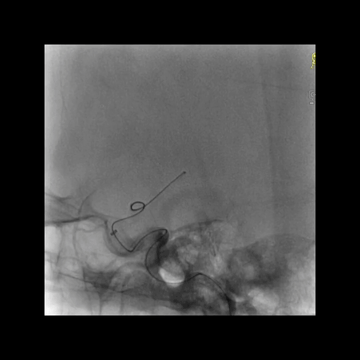

其次,这个患者血栓不仅坚韧而且比较大,第一次抽拉结合取栓后,5F中间管头端虽然吸住了血栓,但嵌合不牢固,负压回撤中间管时血栓脱落卡在ICA后交通开口处。此坚韧血栓再次导致微导丝通过困难,微导丝成袢后才最终通过。

血栓坚硬,微导丝最终成袢通过闭塞位置,微导管跟进进入M1,释放支架。